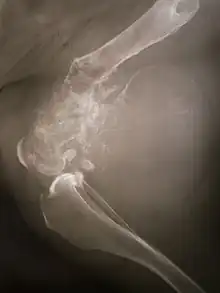

La tumeur peut être localisée à l'extrémité de l'os long. Le plus souvent, elle affecte l'extrémité proximale du tibia ou de l'humérus, ou l'extrémité distale du fémur. L'ostéosarcome tend à affecter les régions autour du genou dans 60 % des cas, dans 15 % des cas c'est autour de la hanche, 10 % à l'épaule et 8 % dans la mâchoire.

La tumeur est solide, dure, irrégulière, (décrite en « sapin » ou en « rayon de soleil » sur les examens aux rayons X) en raison des spicules tumorales d'os calcifiés rayonnant en angle droit. Ces angles droits forment ce que l'on appelle un triangle de Codman. Les tissus environnants sont infiltrés.